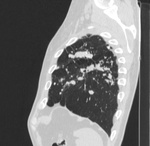

Пациент, впервые заболел в 02 году в ЗК, после рецидив в 07, потом в 11году. Сейчас состоит по активной группе с диагнозом: ФКТЛ легких , 1А (-)ГДУ. А по КТ оказалось, что все и не плохо.

Кроме ФКТ, думаю, что ещё и множество туберкулём. Или это очагами называете? Если туберкулёмы, то в 6-ке справа похоже на распад.